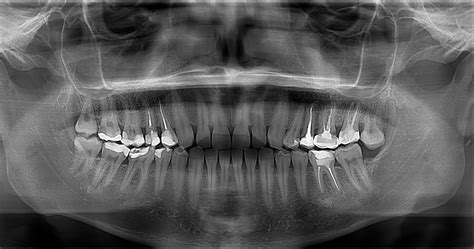

Además de la entrevista clínica, se realizan radiografías dentales para obtener una imagen detallada de las estructuras dentales y óseas. Las radiografías permiten identificar la posición y la relación entre los dientes, así como la presencia de cualquier patología o anomalía. Esto es especialmente importante en casos de dientes retenidos o fracturados, donde las radiografías proporcionan información crucial para planificar la extracción.

Por otro lado, en el caso de los molares inferiores, es fundamental evaluar la distancia entre el nervio alveolar inferior y el área de extracción. Esto es crucial para prevenir lesiones en el nervio durante el procedimiento. La evaluación radiográfica cuidadosa ayudará a determinar la posición exacta del nervio y a planificar la extracción de manera segura.